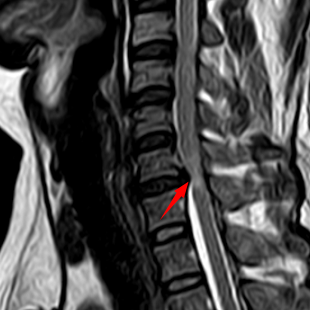

颈椎MRI提示C6-C7平面脊髓受压、变性